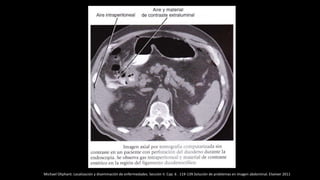

TC con contraste de paciente en la que se observa acumulación de aire por neumoperitoneo debido a

perforación de ulcus duodenal. Obsérvese la burbuja de aire que señala el punto de perforación.

E. Ballesteros Díaz, Patología mesentérica y peritoneal: desde la inflamación hasta la neo formación Seram2012/S-1242